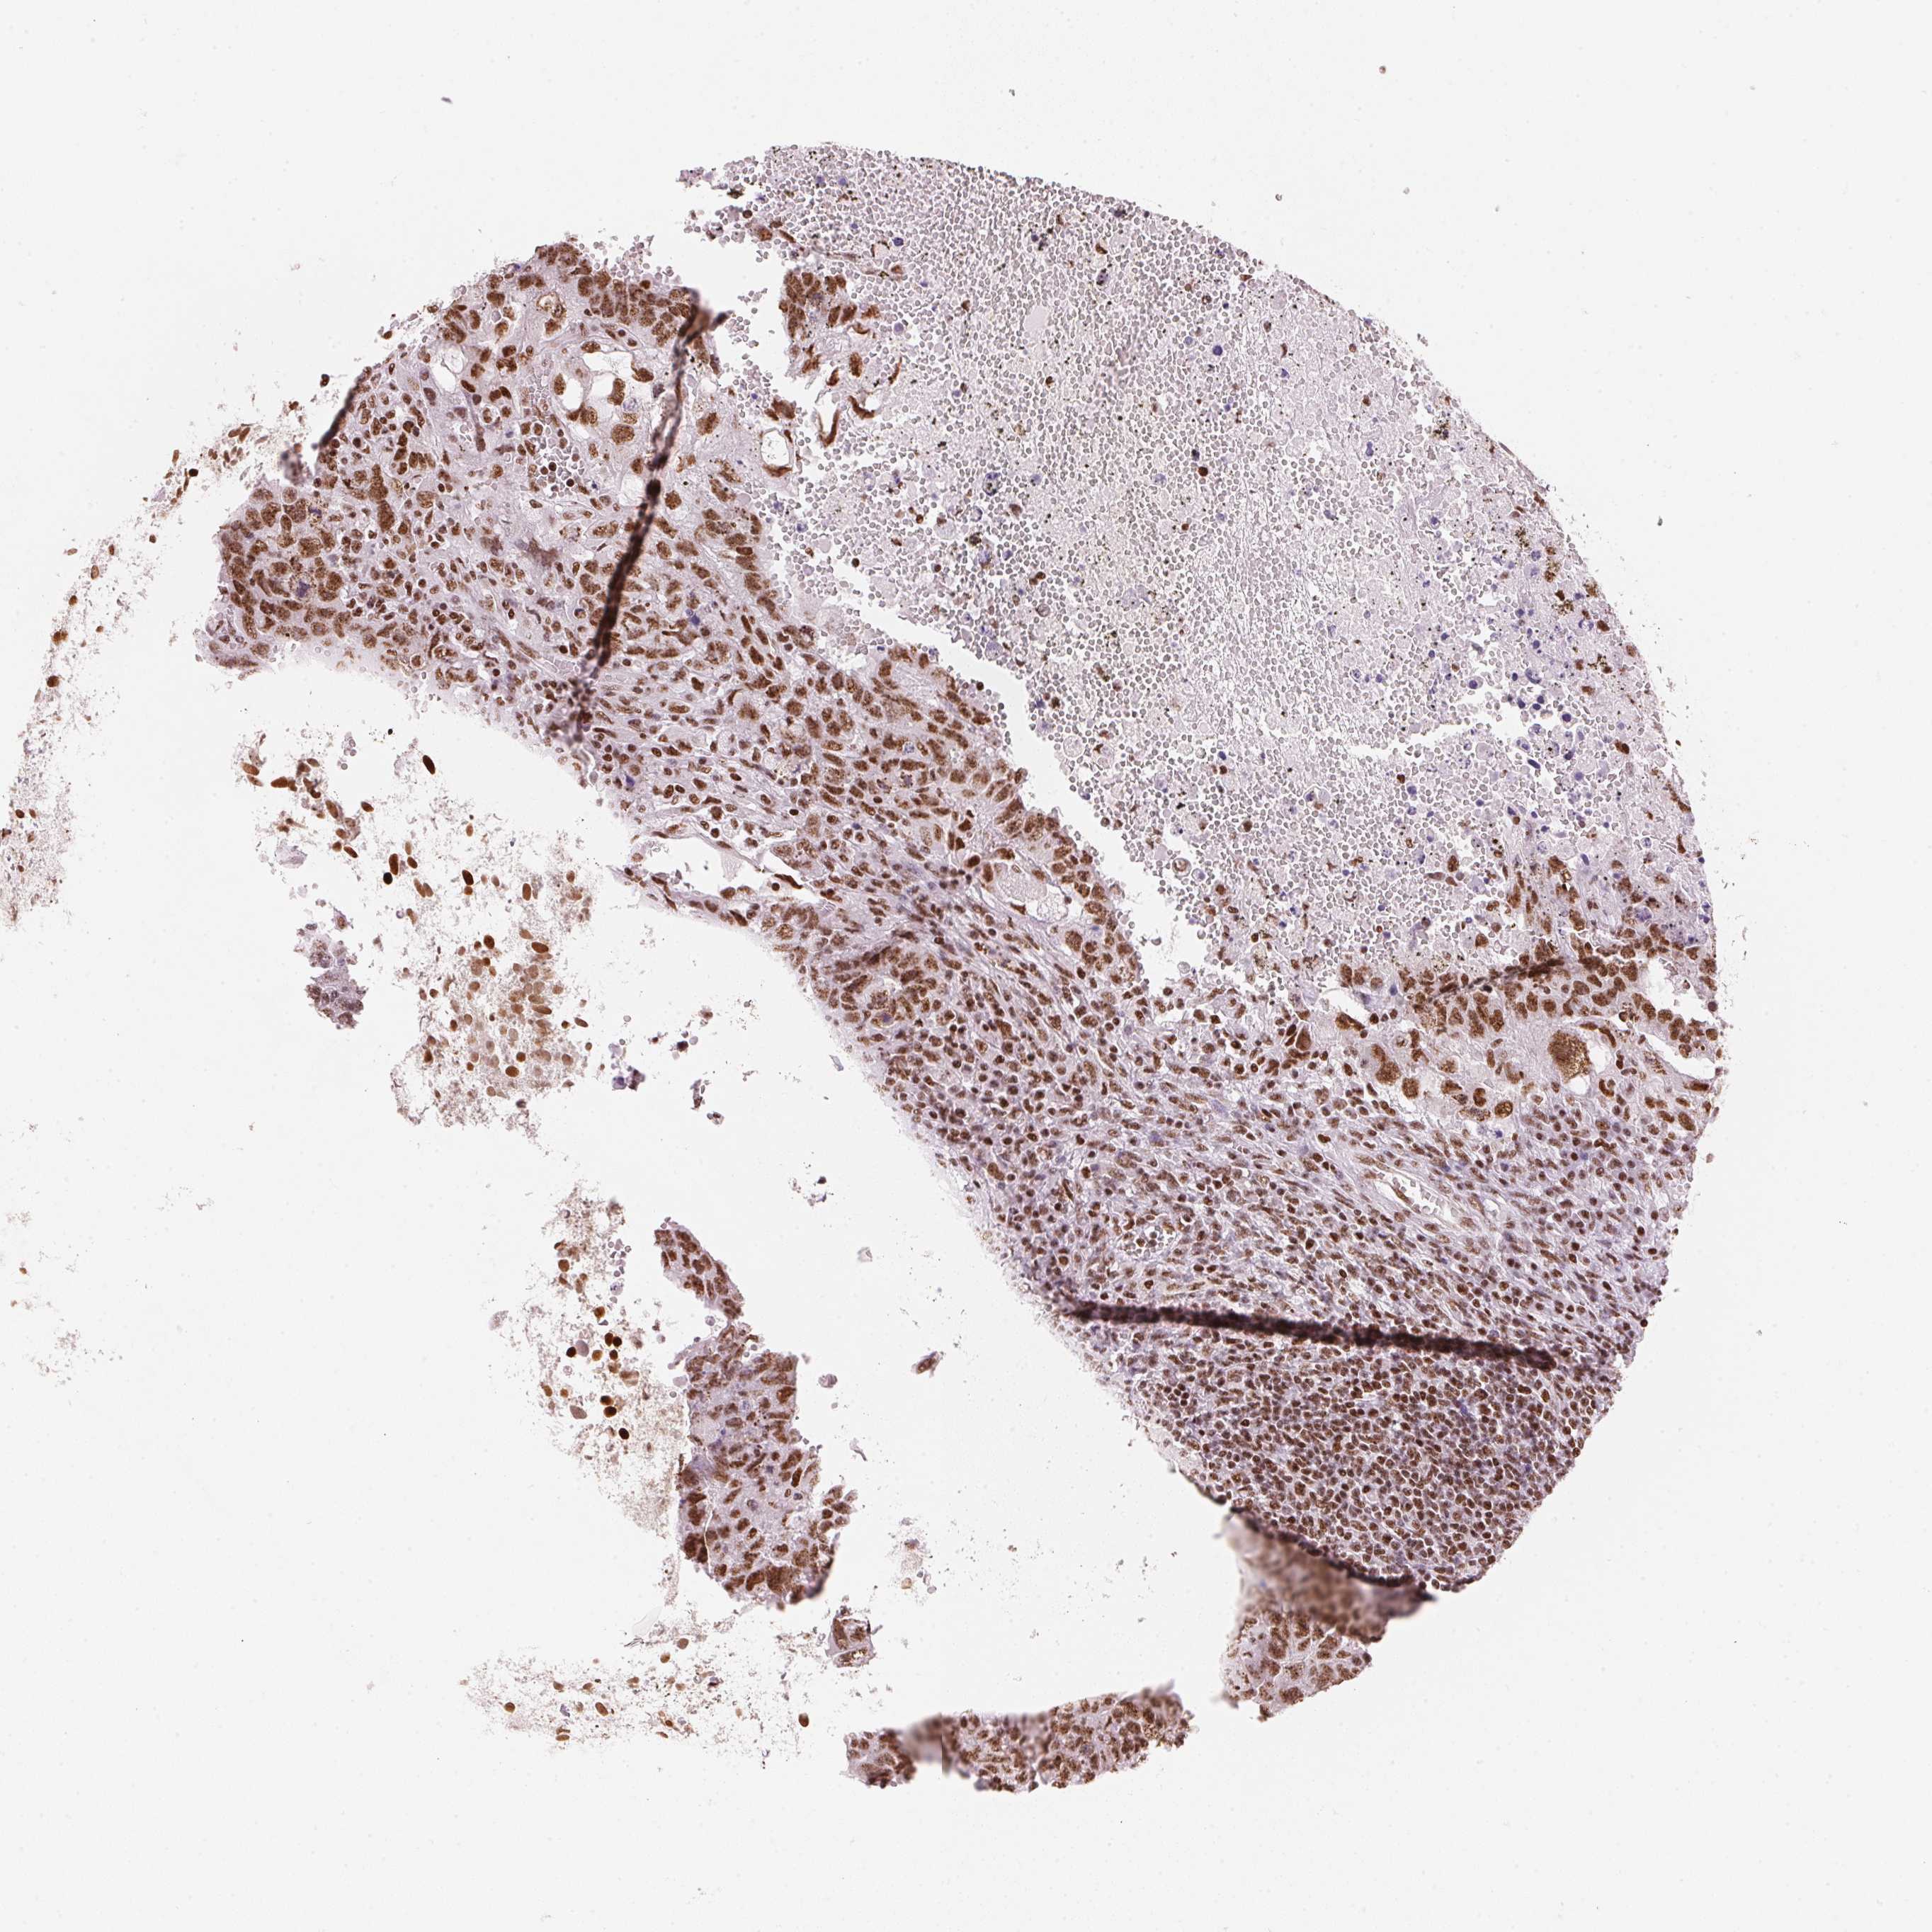

TESTIS CANCER - Protein expressioni

A mouse-over function shows sample information and annotation data. Click on an image to view it in a full screen mode. Samples can be filtered based on level of antibody staining by selecting one or several of the following categories: high, medium, low and not detected. The assay and annotation is described here.

Note that samples used for immunohistochemistry by the Human Protein Atlas do not correspond to samples in the TCGA dataset.

Antibody stainingi

Antibody staining in the annotated cell types in the current human tissue is reported as not detected, low, medium, or high, based on conventional immunohistochemistry profiling in selected tissues. This score is based on the combination of the staining intensity and fraction of stained cells.

Each image is clickable and will lead to virtual microscopy that enables deeper exploration of all samples and also displays staining intensity scores, fraction scores and subcellular localization as well as patient and tissue information for each sample.

Antibody HPA061593

Antibody CAB016327

Staining

High

Medium

Low

Not detected

Intensity

Strong

Moderate

Weak

Negative

Quantity

>75%

75%-25%

<25%

None

Location

Nuclear

Cytoplasmic/membranous

Cytoplasmic/membranous,nuclear

Seminoma, NOS

Carcinoma, Embryonal, NOS